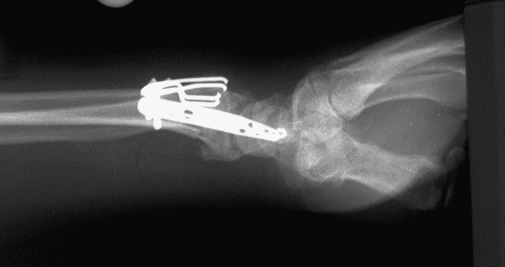

Case 2 Postop